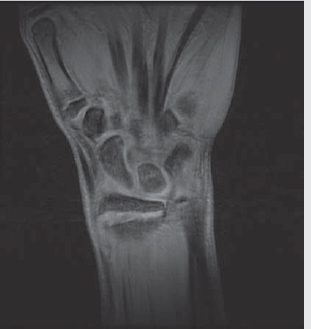

Scapholunate ligament tear

On X-ray and CT, can be seen as widening of scapholunate interval (► Fig. 4.5).

On MRI, T2 hyperintense (fluid bright) gap instead of expected T2 hypointense ligament.